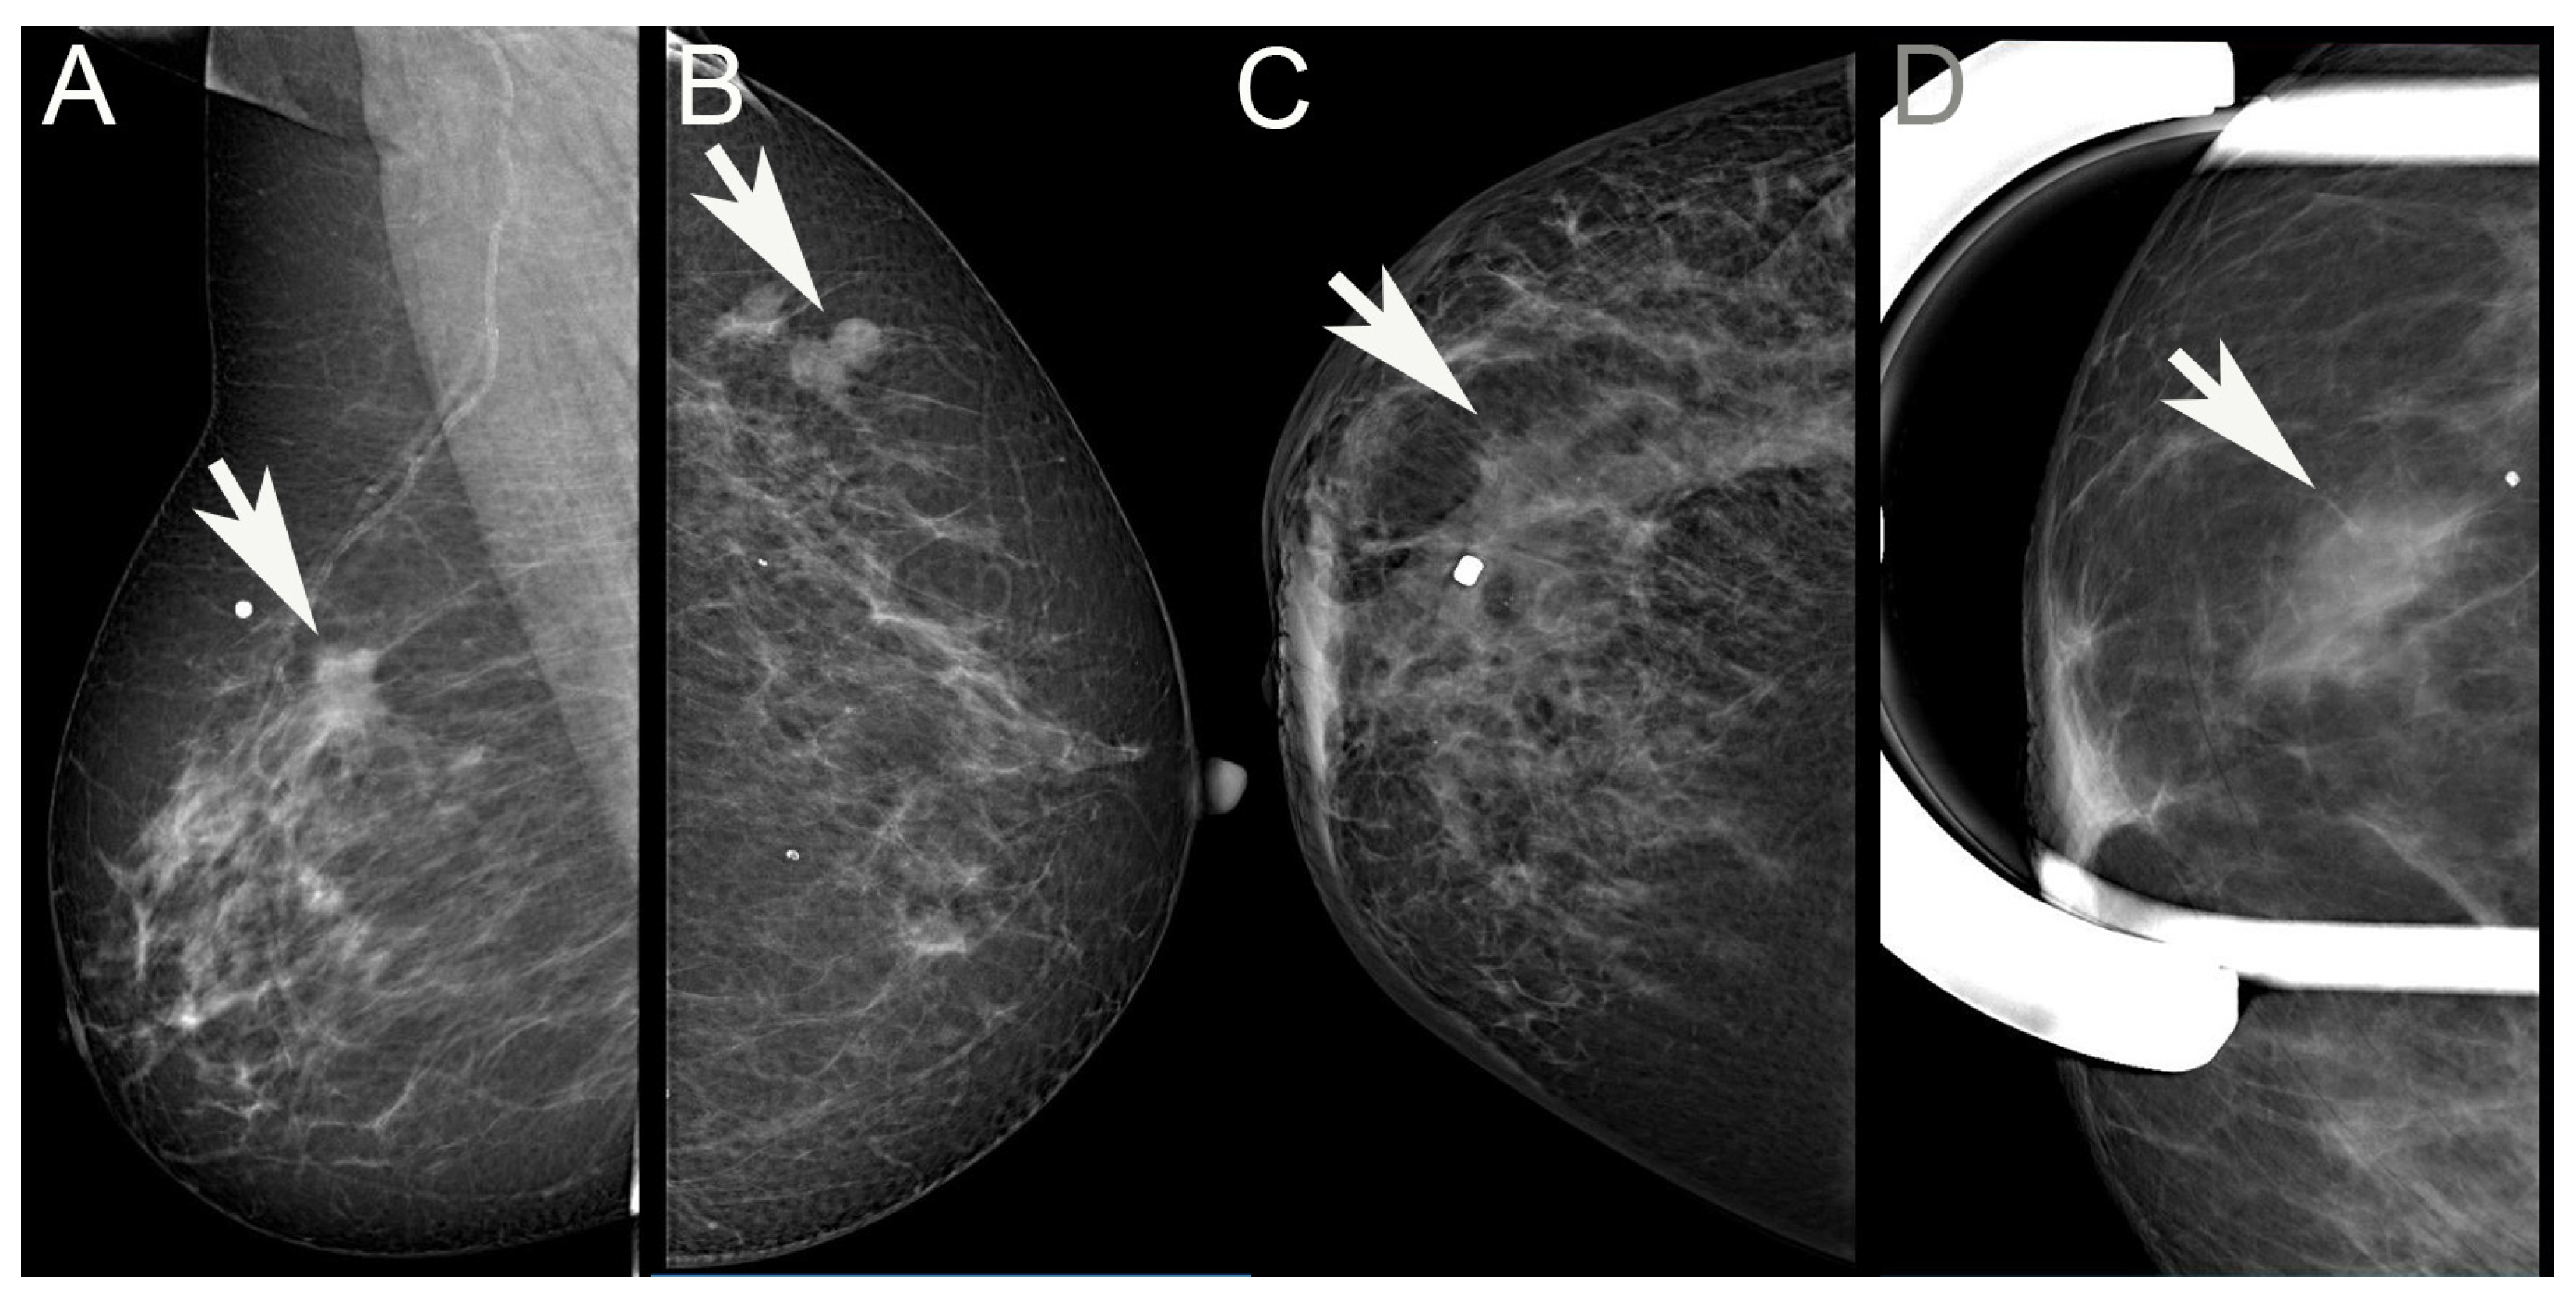

Figure 1.

Examples of visible mammographic alterations evaluated in the study. (A): Spiculated mass; (B): Lobulated/circumscribed mass; (C): Architectural distortion; (D): Increased density. (Arrows point to the lesions. White dots label the cutaneous area where the patient palpated the lesions).